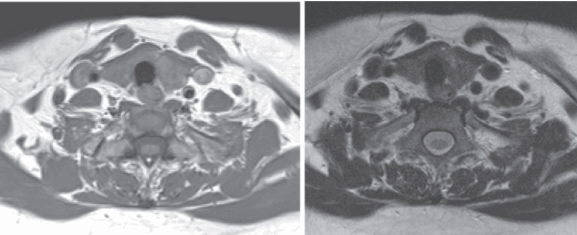

Снимки МРТ мягких тканей шеи

Проведение магнитнорезонансной томографии с использованием различных режимов повышает информативность исследования рыхлых элементов. Изучение особенностей кровоснабжения зоны интереса и диагностика новообразований требуют применения контрастного раствора. В качестве «окрашивающего» препарата используют хелаты гадолиния.

Мягкие ткани шеи на МРТ